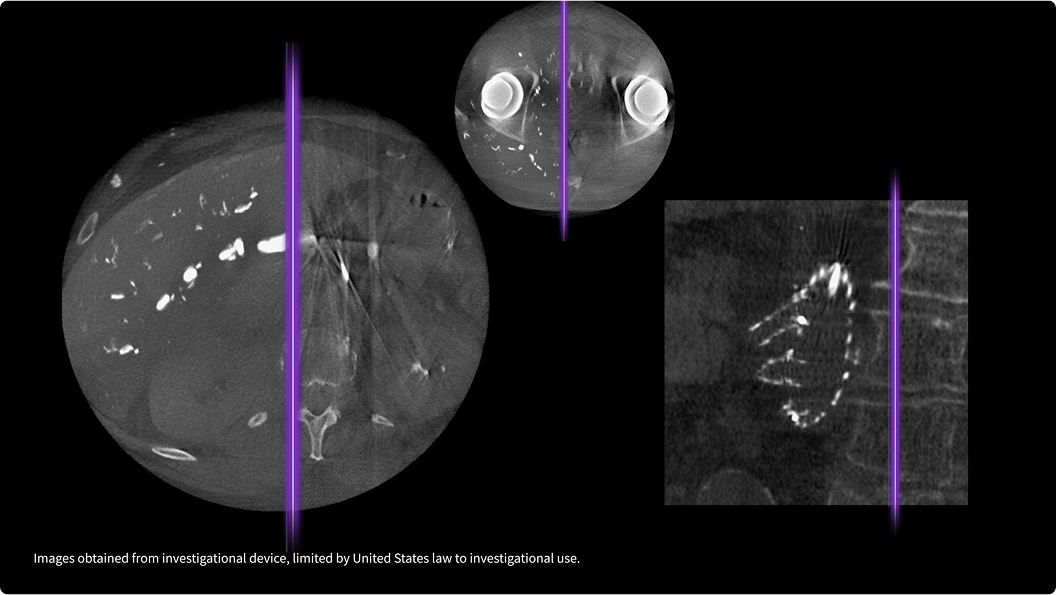

Achieve a new standard of color Doppler with Radiantflow™ - delivering easy, fast visualization of even the tiniest of vessels.

Dynamically apply targeted transparency to rendered structures for a more thorough view of anatomy from a solid surface structure to developing internal anatomy.